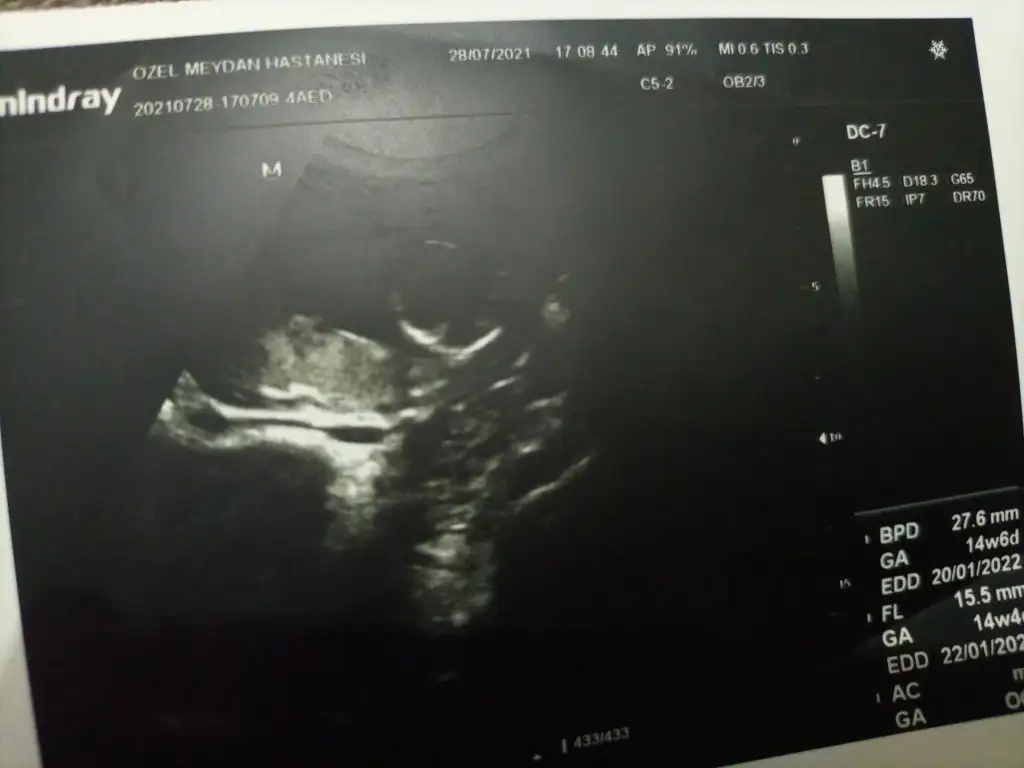

Doktor simdilik kiz diyelim dedi ama bakalm sabaha randevumuz var gozukurse yazicam insallah saglikla gelsin de hic farketmez sagolasin cevabin icin bide son ultrasonu atayim ona da bakiverErkek gibi

Doktor simdilik kiz diyelim dedi ama bakalm sabaha randevumuz var gozukurse yazicam insallah saglikla gelsin de hic farketmez sagolasin cevabin icin bide son ultrasonu atayim ona da bakiver![]()

Evet burada bacak arası boş görünüyor sağlıkla gelsin prenses

Erkek görünüyorEki Görüntüle 2893317 12+4 haftalık cinsiyet tahmini alabilir miyim ?